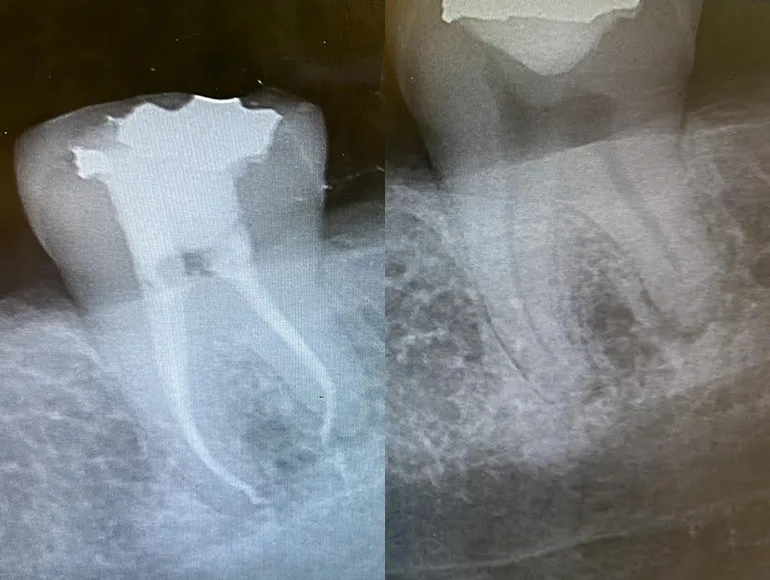

Teeth With Unconventional Number of Roots or Canals

Case by Dr. Taha Azimaie: Identifying unconventional number of roots and canals is the key in long term survival of the tooth. Tooth number 4, upper right premolar, usually have 1 pulp chamber, 1 root and 1 canal. This tooth have complex shape with 2 pulp chambers and 3 canal.